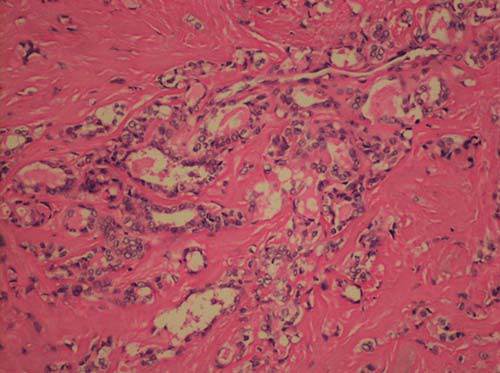

Paciente masculino de 54 años que inició su padecimiento actual con aparición de un tumor cervical anterior de seis meses de evolución, de 3 × 5 centímetros de diámetro. Ultrasonido de tiroides con nódulo tiroideo derecho de 5.0 × 3.8 × 4.0 cm, TIRADS 4c, con lesión tiroidea compleja sólido-quístico-septos y adenopatías sospechosas en nivel VI del cuello. Se realizó diagnóstico de carcinoma papilar de tiroides mediante biopsia por aspiración con aguja fina (BAAF) del nódulo tiroideo; el estudio de laboratorio para función tiroidea resultó dentro de los parámetros normales. Se llevó a cabo tiroidectomía total + resección de quiste tirogloso (Figura 1) con reporte patológico de carcinoma papilar variante convencional multifocal con desmoplasia moderada que infiltraba la cápsula tiroidea (Figura 2) y fibras del músculo estriado pretiroideo adyacente (Figura 3), tumor de lóbulo derecho de 2 × 1.5 × 1.3 cm, tumor de lóbulo izquierdo de 3.5 × 3 × 4 cm (Figura 4). Se discutió en junta multidisciplinaria, donde se decidió que era candidato a ablación con I-131. Después del tratamiento con I-131, se mantuvo sin complicaciones y con niveles de Tg < 0.2.